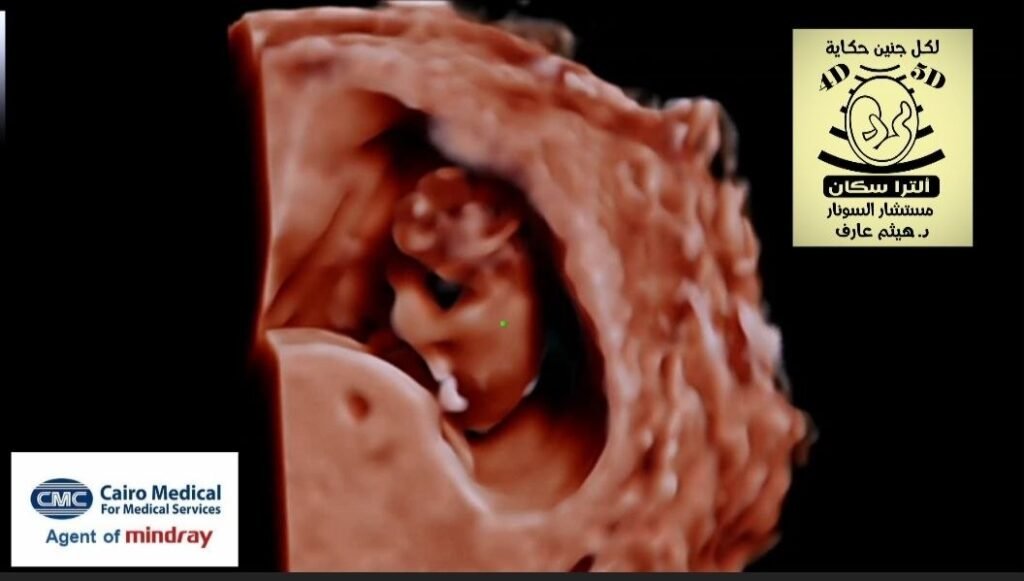

Diandric triploidy fetal ultrasound

Diandric triploidy is a genetic abnormality where a fetus has 69 chromosomes instead of 46, with the extra set derived from the father (69,XXX, 69,XXY, or 69,XYY), often resulting from dispermy. This condition typically causes early first-trimester miscarriage, presenting with a partially hydatidiform mole, a large, cystic placenta, and anomalous FGR fetus.

• Clinical Presentation: Associated with partial hydatidiform mole, characterized by a large cystic placenta and a fetus with potential severe, asymmetrical growth restriction .